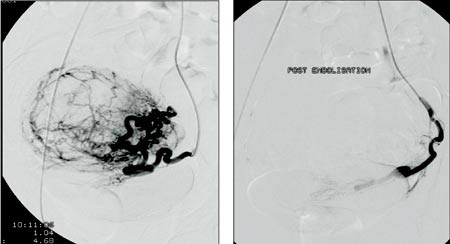

Arteria femoralis communis punkteres perkutant i høyre lyske og a. iliaca interna kateteriseres med 4 F-kateter med fleksibel tupp. Deretter tilstrebes selektiv kateterisering av a. uterina slik at den cervikovaginale gren av arterien bevares ved emboliseringen. Røntgenkontrast blandet med polyvinylalkoholpartikler av 355 – 500 m størrelse injiseres langsomt. Injiseringen avsluttes når det ikke lenger påvises sirkulasjon til myomet eller myomene. Samme prosedyre gjentas på motsatt side via samme tilgang i lysken. Dermed unngås nytt innstikk. Det er viktig å påvise eventuell kollateral sirkulasjon fra a. uterina til det ene eller begge adnekser fordi det kan redusere emboliseringseffekten. I slike tilfeller kan det være aktuelt først å embolisere kollateralene. Ved kateteriseringen kan det oppstå arteriespasme i området der katerspissen befinner seg. Dette kan behandles med lokal injeksjon av nitroglyserin. Avslutningsvis utføres aortagrafi for å utelukke eventuell sirkulasjon til myom fra a. ovarica. Figur 1 viser selektiv angiografi av venstre a. uterina med oppladning i stort myom før og etter embolisering. Figur 2 viser stort intramuralt myom før og ni måneder etter embolisering.